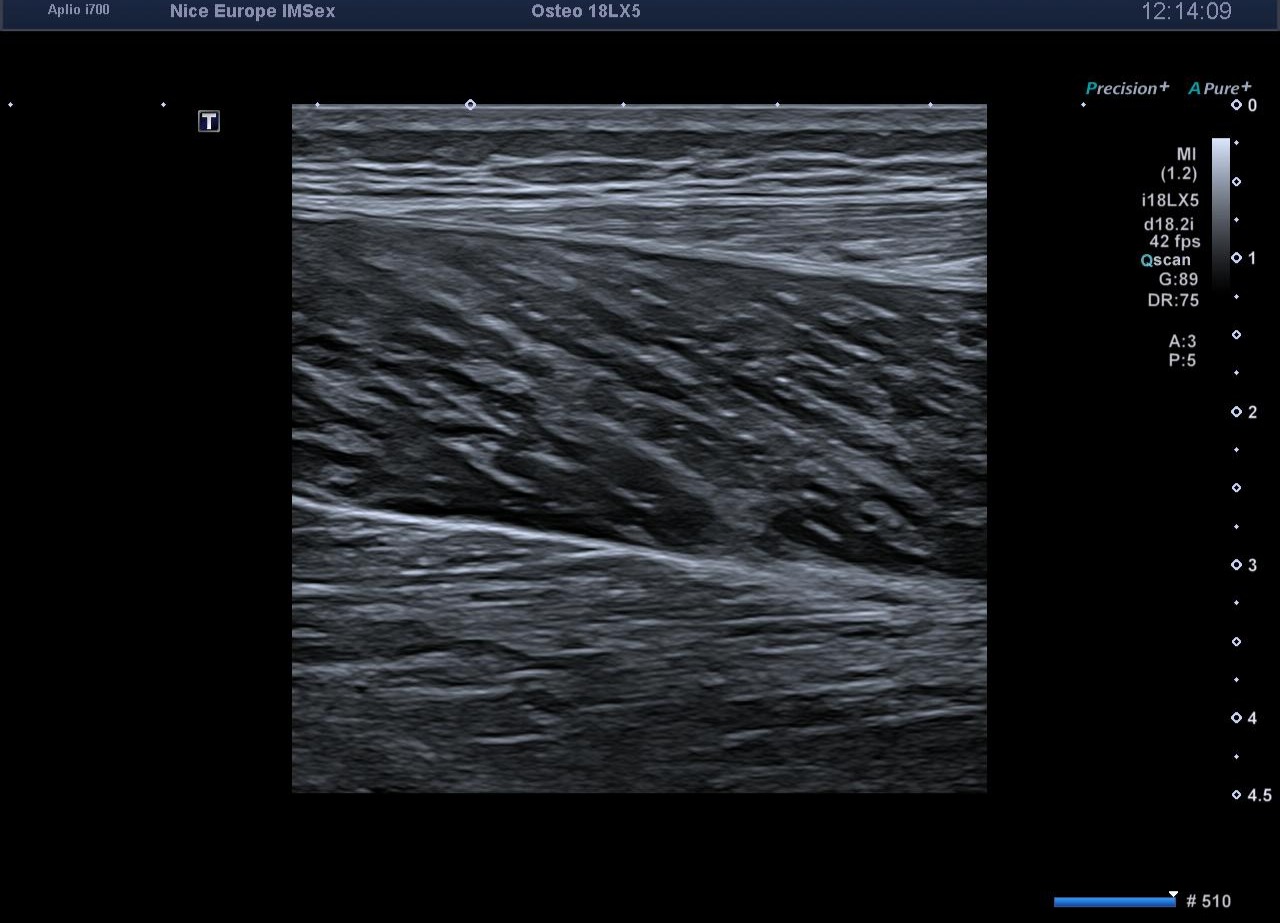

L’exploration statique haute résolution de la cheville et du mollet s'avère strictement normale. Les tendons calcanéens (d'Achille) présentent une écho-structure fibrillaire parfaitement conservée, sans épaississement focal, ni hyperhémie au Doppler énergie. L'exploration de la loge postérieure montre des ventres musculaires gastrocnémiens et soléaires volumineux mais d'échostructure normale, tout comme les jonctions myo-aponévrotiques. L'artère poplitée est perméable au repos, avec un flux Doppler triphasique physiologique.